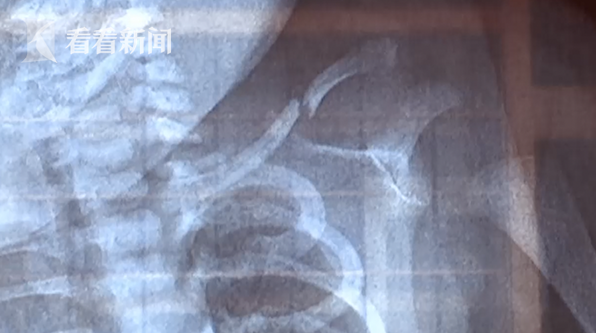

據看看新聞9月14日報道,安徽阜陽市的李女士在9月9號凌晨生下一名女嬰,本是讓全家開心的重大時刻,卻很快又讓全家愁眉緊鎖,因為這個新誕生的孩子,鎖骨骨折。

然而,當孩子生下來後,意外出現了。李女士和家人認為,是醫院的工作人員在生產時,將孩子拉出來的過程中,因為用力不當,導致孩子鎖骨骨折。

李女士的母親:“就是醫生拉着鎖骨硬拉出來拉斷的,手臂這還青了這麼長,肯定是醫院的責任。”